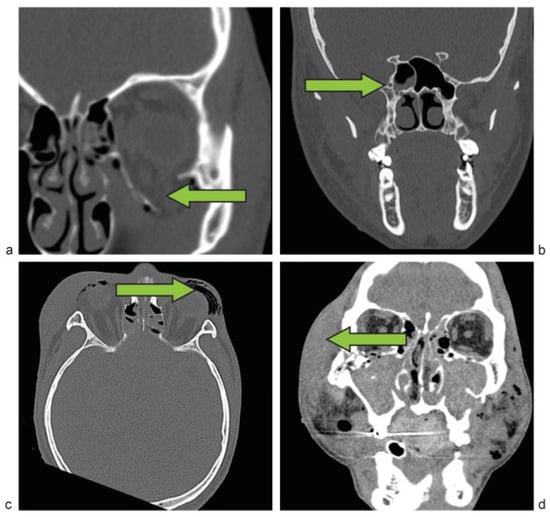

Figure 1.

Direct signs of orbital fractures. (a) Right orbital floor fracture with an abrupt change in bone density. (b) Right orbital floor fracture with an interruption of cortical bone continuity. (c) Abnormal angulation between the right orbital floor and a displaced bone fragment.

Figure 2.

Indirect signs of orbital fractures. (a) Coronal view of a left orbital floor fracture with opacification of the left maxillary sinus. (b) Presence of an air-fluid level in the right sphenoid sinus. (c) Intraorbital and periorbital subcutaneous emphysema in a bilateral orbital fracture. (d) Surrounding soft tissue edema in a patient with multiple facial fractures.